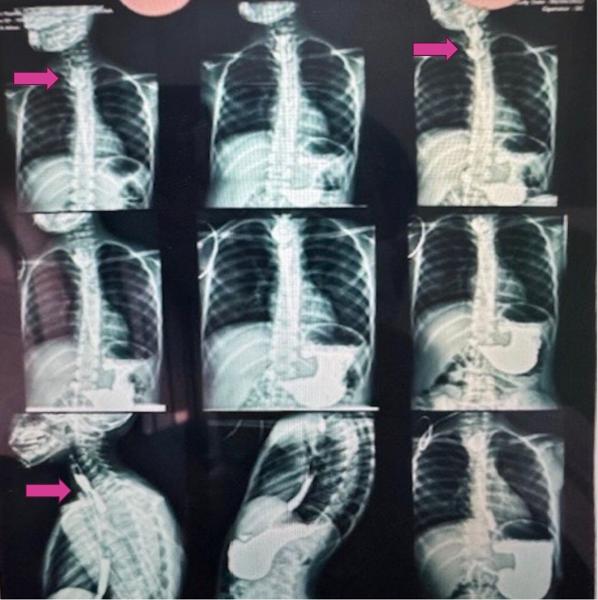

Estudios iniciales de motilidad y anatomía: Seriada Esofagogástrica muestra imagen diverticular en pared posterior del esófago cervical con retención de contraste que mide (42mm×48mm×14 mm).

En la seriada, colección de contraste adyacente a la luz, de contornos lisos, implantación en cara posterior cervical, que sugiere cavidad comunicante; mide (42mm×48mm×14 mm.) En duplicaciones, el esofagograma puede mostrar defecto de repleción o cavidad comunicante/adyacente según el grado de comunicación.

Retención de medio de contraste en la cavidad

Persistencia del contraste en la lesión durante la seriada, compatible con bolsillo quístico o diverticular con vaciamiento lento; en quistes de duplicación, la retención depende de la comunicación y del contenido viscoso.

ESOFAGOGRAMA puede evidenciar cavidad adyacente/comunicante con retención;

imagen de cavidad que se llena parcial o totalmente con contraste, puede persistir el contraste tras la deglución, con vaciamiento lento, defecto de repleción extrínseco si no hay comunicación.